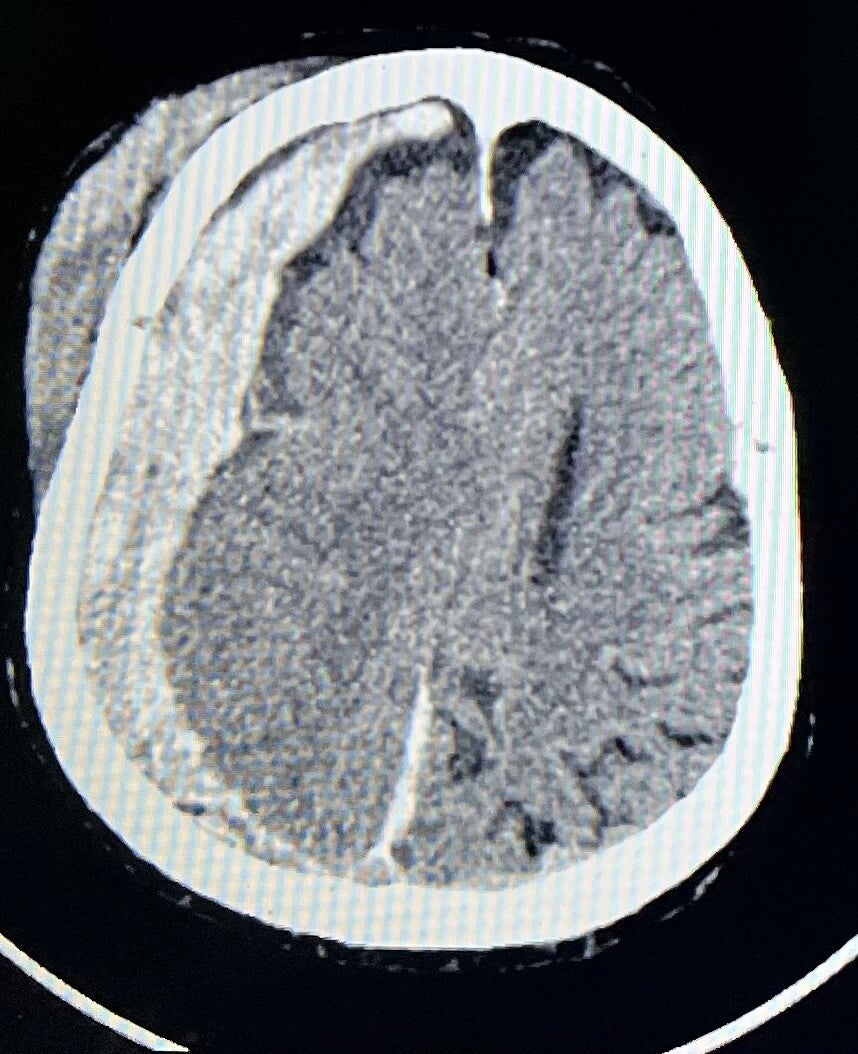

- Hematomas subdurales y epidurales.